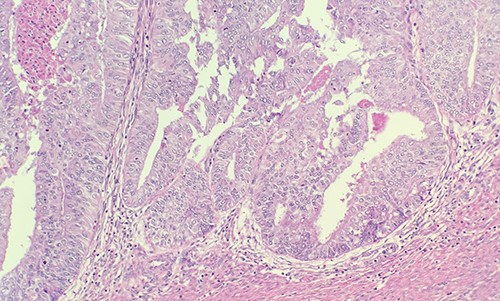

Patient was admitted for hysterectomy for endometrial carcinoma. There is a mass lesion measuring 4.3 × 4 cm located in right ovary indicating metastatic from uterine endometrial primary on image study. Microscopic examination of endometrial reveals endometrial adenocarcinoma, endometrioid type, FIGO Grade 2 (Fig. 1). Microscopic examination of ovary shows solid growth of tumor cells with angulated pale nuclei and nuclei grooves (Fig. 2). Tumor cells are positive for CD56, CD99, Calretinin (Fig. 3) and inhibin, combined with morphological features; this immunoprofile supports the diagnosis of granulosa cell tumor, adult type.

Microscopic examination of endometrial reveals endometrial adenocarcinoma, endometrioid type, FIGO Grade 2 (H&E ×20).